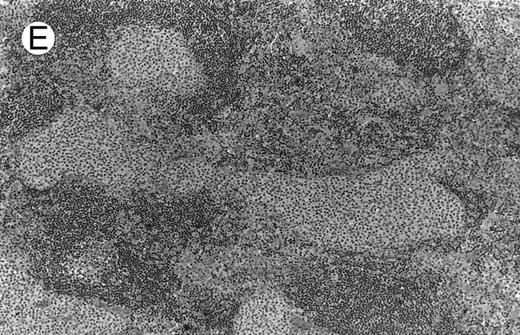

Low-grade marginal zone B-cell lymphoma (MZL; REAL classification)9 comprised the largest number of cases (n = 12). Nine of them were low-grade MALT type lymphomas involving parotid, stomach, bronchus, buccal mucosa, and skin. The histological pattern was relatively homogeneous, showing diffuse lymphoid infiltrates that included small lymphocytes with round nuclei or with plasma-cell differentiation and/or centrocyte-like cells with indented nuclei (Fig 1A). Lymphoepithelial lesions were observed in each case, regardless of the tissue involved (Fig 1B). Monocytoid cells characterized by a larger cytoplasm and a slightly irregular nucleus were mixed with centrocyte-like cells in 2 cases of MALT lymphoma arising in the parotid (cases no. 3 and 15). There were also scattered occasional large cells (centroblast or immunoblast). In cases no. 3, 6, and 15, remnants of germinal centers with partial follicular colonization were observed (Fig 1C). Beside these 9 low-grade-type mucosal lymphomas, 3 nodal lymphomas (cases no. 8, 10, and 14) had histological features similar to that of low-grade MALT type lymphoma because they showed a typical lymphoplasmacytoid infiltration with a variable proportion of blasts. In 2 cases, the presence of numerous immunoblasts or centroblasts, mixed with small lymphoplasmacytoid cells or plasma cells, indicated an evolution to a more aggressive lymphoma (Fig 1D). The third nodal lymphoma showed a small lymphocytic or lymphoplasmacytoid diffuse infiltrate associated with intrasinusal large nests of monocytoid cells. This histological picture is characteristic of monocytoid B-cell lymphoma (MBLC; Fig 1E).

(D) Case no. 10. Immunocytoma in lymph node. The infiltrate is composed of small lymphocytes, plasma cells and blasts. (E) Case no. 14. Monocytoid B-cell lymphoma in a cervical lymph node with a monocytoid component located in dilated sinuses.